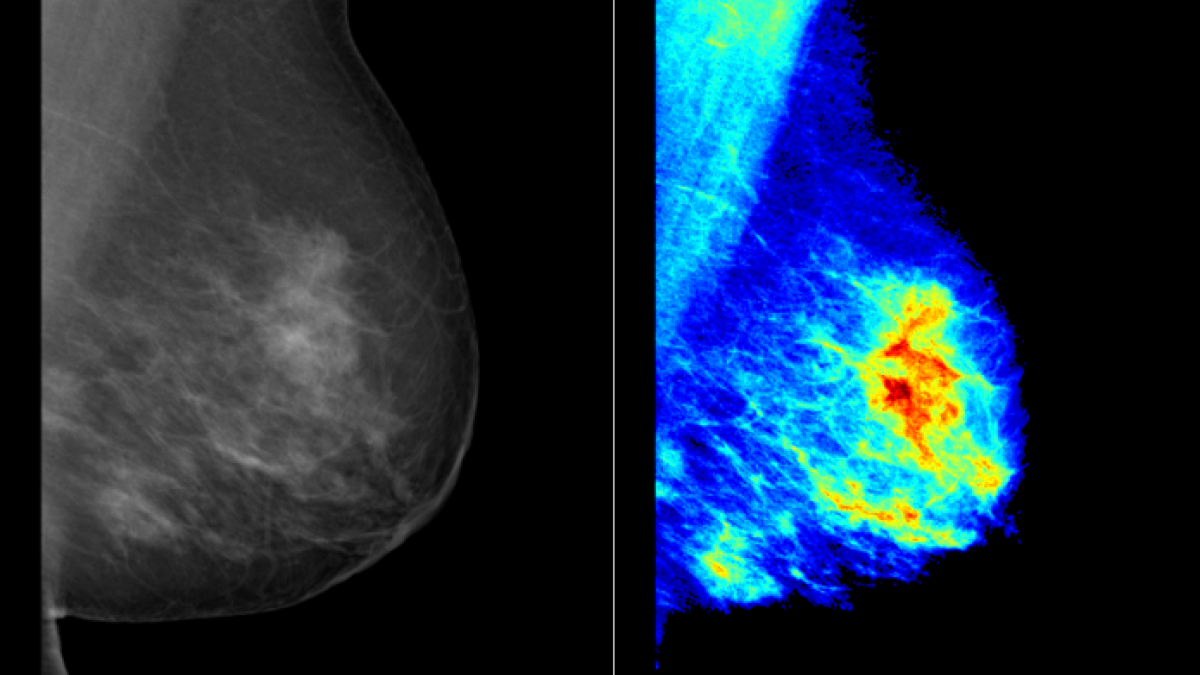

Areas of specialism: X-ray mammography and hyperspectral imaging.

Research funding and collaborators: £65,000 PhD funding for “quantitative SPECT imaging" (Surrey-NPL scheme, 2017-20), £72,000 PhD funding for “hyperspectral X-ray imaging for breast density measurement” (STFC Cancer Diagnosis Network and Surrey DCSA, 2020-2024).

Areas of specialism: Diagnostic imaging, artificial intelligence and computer vision for healthcare, digital pathology, PET/CT, mammography, non-contact sleep monitoring, virtual clinical trials, veterinary imaging and veterinary healthcare, one health.